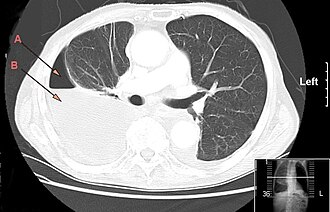

Empijem pleuralne šupljine predstavlja oblik piotoraksa u kojem gusti gnoj ispunjava pleuralnu šupljinu. Empyema pleurae obično uzrokuje širenje infekcije iz pluća. Gnoj pritišće pluća. Upala pluća, apsces pluća, kirurgija toraksa i trauma su najčešći uzroci pojave empijema pleuralne šupljine. Torakocenteza može u rijetkim slučajevima dovesti do empijema.[1][2][3]

Dijagnoza

Tiše disanje ili struganje se može čuti stetoskopom (auskultacija). Na perkusiju (kuckanje) dobije se mukli zvuk na mjestu gdje je šum disanja tiši.

Sljedeće pretrage su potrebne:

- RTG snimak pluća

- CT pluća